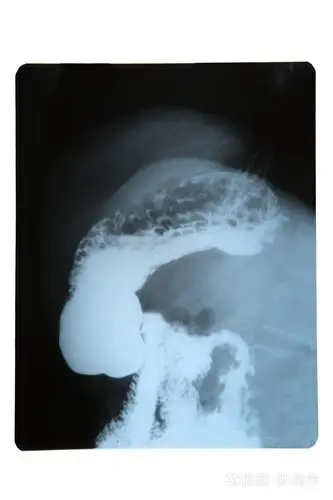

胃下垂的无创治疗

5 分钟读懂消化道造影片(胃篇)

答对这 8 个问题 胃部读片才算过关